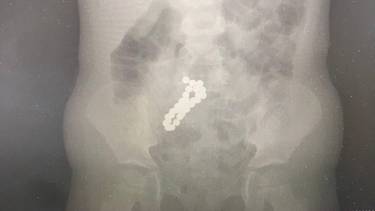

Подмосковные врачи достали из кишечника четырехлетней девочки 30 магнитов

Фото: Пресс-служба Министерства здравоохранения Московской области

Специалисты Московского областного центра охраны материнства и детства (МОЦОМД) достали из кишечника четырехлетней девочки 30 магнитов. Об этом во вторник, 3 марта, сообщили в пресс-службе регионального министерства здравоохранения.

Родители ребенка вызвали скорую помощь, так как у девочки наблюдалась сильная рвота. Ранее они обнаружили, что из дома бесследно пропал магнитный конструктор.

— Врачи провели исследования и обнаружили в тонком кишечнике девочки 30 магнитных шариков диаметров по десять миллиметров. Магниты извлекли лапароскопически — через маленькие проколы, — объяснил врач детского хирургического отделения Сергей Борисов.

Операция прошла успешно, состояние ребенка сразу же улучшилось. Сейчас девочка уже лечится дома, уточнили на сайте ведомства.